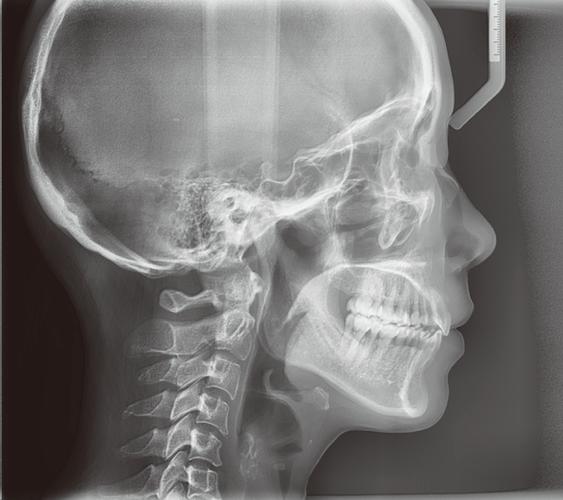

正畸治疗的核心是精准诊断与个性化方案设计,而头颅侧位片作为评估颌面部骨骼、牙齿及软组织形态的关键影像资料,其分析效率与准确性直接影响治疗效果,传统头影测量依赖人工描点、手工计算,存在操作繁琐、主观性强、数据可重复性低等问题,正畸头颅侧位软件的出现,通过数字化、智能化技术重构了头影测量流程,成为现代正畸诊疗的重要工具。

头影测量分析是软件的核心功能,分为自动、半自动及手动三种模式,自动模式下,软件基于深度学习模型(如卷积神经网络CNN)识别解剖标志点,通过10万+标注临床图像训练,实现对蝶鞍点、鼻根点、上齿槽座点、下齿槽座点等20余个关键标志点的定位,准确率可达95%以上;半自动模式允许医生对AI识别结果进行微调,解决罕见解剖结构(如蝶鞍钙化、颌骨囊肿)的识别偏差;手动模式则支持自定义标志点,满足特殊研究需求,测量指标覆盖经典头影测量项目(如SNA角、SNB角、ANB角、U1-NA距、L1-NB距等)及个性化参数,软件自动计算并生成数据表格,避免人工计算误差。

在临床应用中,软件的价值贯穿诊疗全程,诊断阶段,通过快速分析颌骨畸形类型(如骨性Ⅱ类错颌表现为SNA角>82°、ANB角>5°)、牙齿拥挤度(用牙冠宽度总和与牙弓弧长差值计算)及面部软组织突度(如鼻唇角<90°提示上唇前突),明确病因与分类;方案设计阶段,可模拟不同矫治器的效果(如隐形矫治器 vs 传统托槽),或预测种植支抗辅助上颌前内收的骨骼改建量;疗效评估阶段,通过治疗前后头影测量数据对比(如上中切牙凸距减少3-5mm、下颌平面角变化2-3°),量化矫治效果,为方案调整提供依据,在科研领域,软件可批量提取测量数据,支持错颌畸形流行病学研究、遗传因素分析及矫治技术疗效对比,推动正畸学科发展。